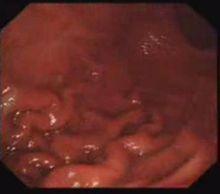

正常胃黏膜形成很多折皺,稱皺襞(gastric folds,plicae gastricae)。體胃大彎處皺襞最明顯,前後壁較少,小彎處則很少見到。胃底部皺襞粗大呈明顯的腦回狀。胃腔注氣後擴張,黏膜隨之伸展。竇部見不到縱行皺襞。

胃皺襞黏膜皺襞:正常胃黏膜形成很多折皺,稱皺襞。皺襞迂曲宛轉互相平行靠攏,自體上部至下部,達竇部時變細並消失。體大彎處皺襞最明顯,前後壁較少,小彎處則很少見到...

解剖結構 臨床套用胃的巨大黏膜皺襞症於1888年由Menetrier氏首先報導,故又稱為Menetrier氏病。Menetrier氏認為此症是由於胃腺的肥大引起胃黏膜皺襞增大。